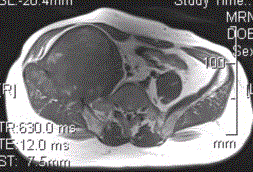

患者男,28岁,右下腹及臀部疼痛5个月余。查体:右髂骨外后侧压痛,右下腹可触及一软组织包块,质韧,固定。行骨盆正位CR、骨盆CT及MR扫描见下图。...

问题 患者男,28岁,右下腹及臀部疼痛5个月余。查体:右髂骨外后侧压痛,右下腹可触及一软组织包块,质韧,固定。行骨盆正位CR、骨盆CT及MR扫描见下图。 对于此病变的征象,描述不正确的是

选项 A.右髂骨翼分叶状溶骨性骨质破坏,边缘清晰硬化,形成巨大软组织肿块 B.右髂骨软组织肿块侵犯右侧腰大肌 C.右髂骨软组织肿块推压右侧腰大肌 D.T2WI示病灶内多发囊状高信号影 E.病灶内可见多发T1、T2均呈低信号的条状影,提示为纤维分隔

答案 B